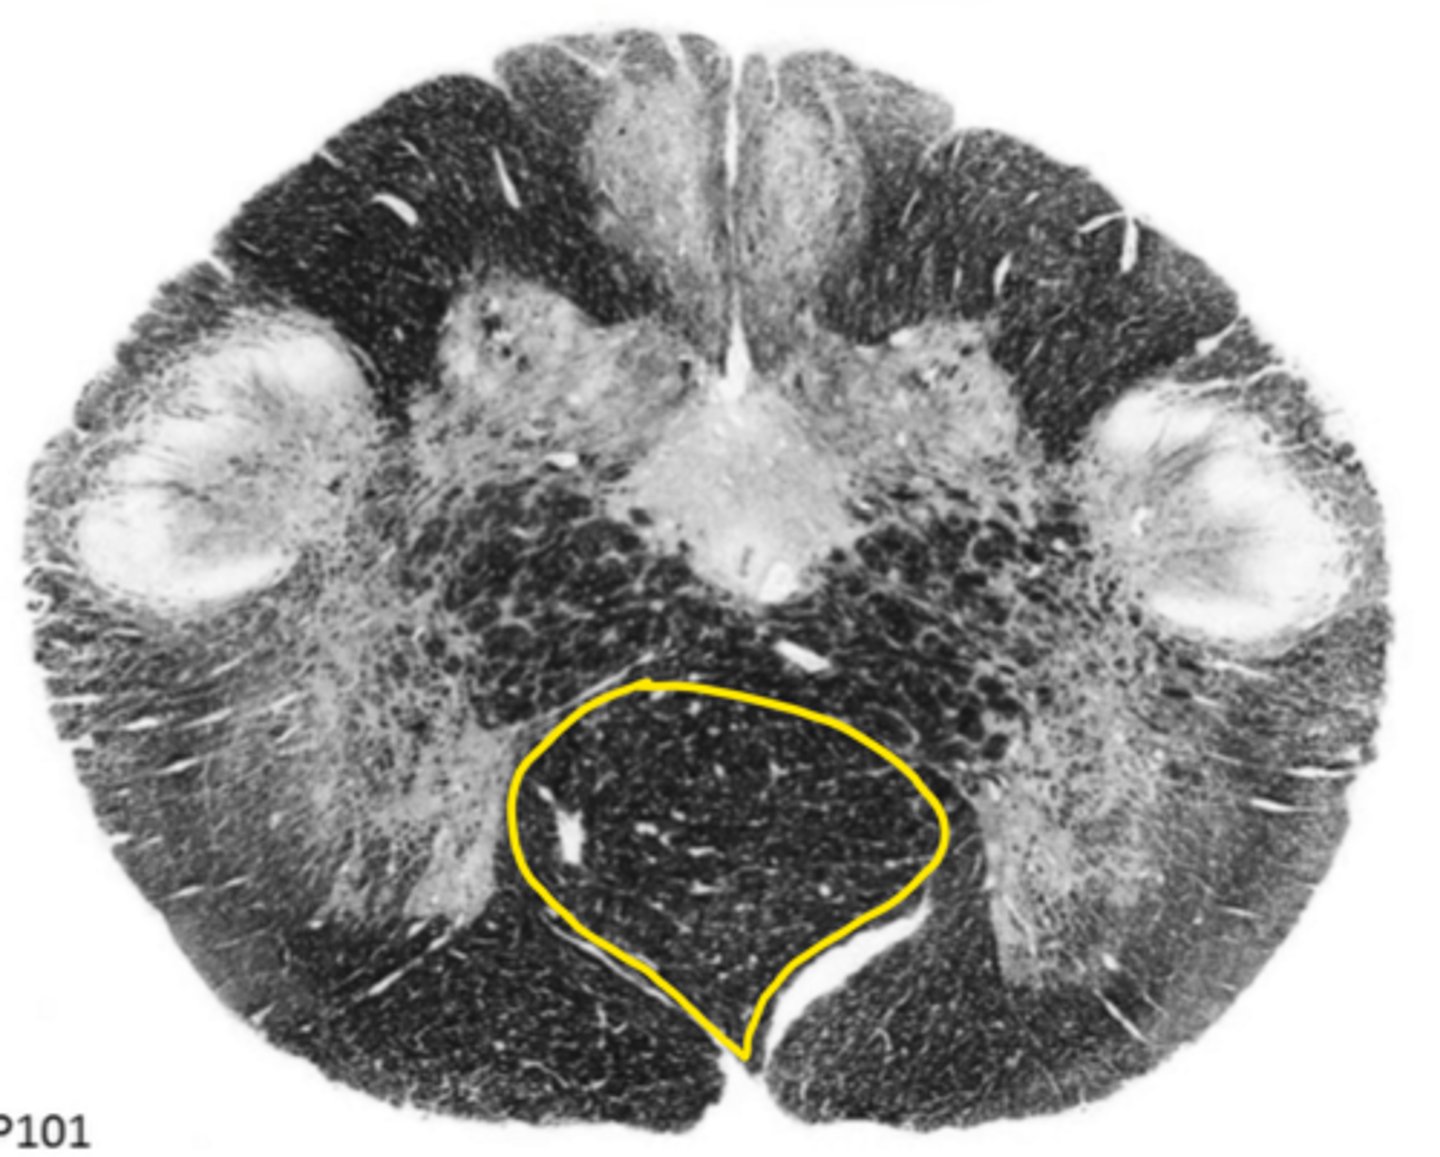

open medulla

ID the brainstem level